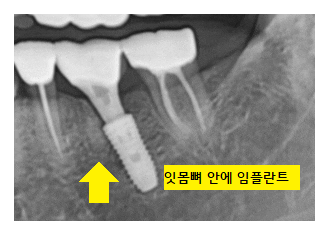

임플란트는 치아 뿌리 부분에 해당합니다.

뼈 안에 심어야 하다 보니

잇몸을 절개 후

뼈를 직접 확인했어야 했는데요.

x-ray 검사를 하더라도

실제 열어봤을 때 다른 경우도 많았습니다.